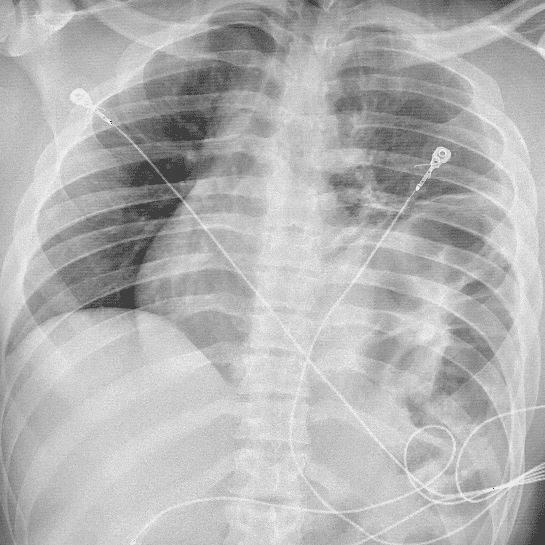

Practice Cases